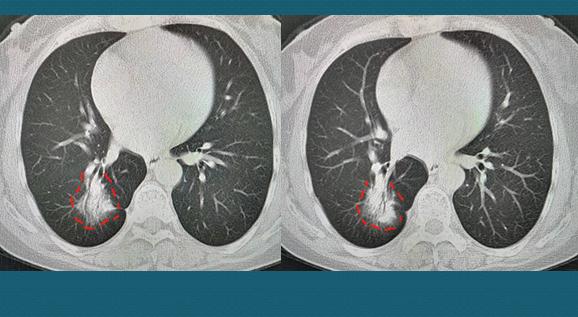

这位女士没有咳嗽症状,因为后背闷痛2周,脊柱外科医生给开了肺部CT,结果发现肺癌:

肿瘤呈混合磨玻璃结节,直径3.3cm,内部课件支气管充气征(通常提示分化较好),边缘可见毛刺和胸膜牵拉,胸腔镜手术,病理是浸润性肺腺癌。

已经3年半了,前天回来复查恢复很好: